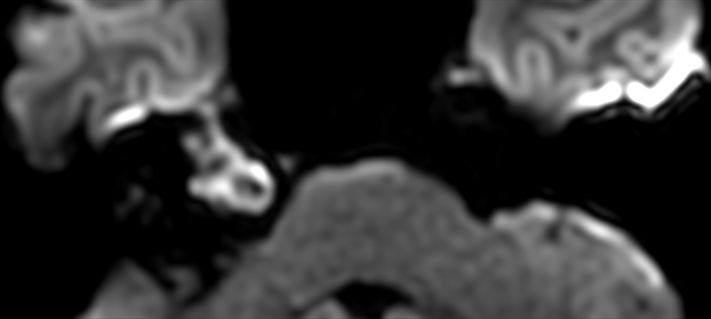

Patient with an IAC lesion. Comparing different DWI methods (EPI, TSE, ZOOM). Compressed SENSE is added to all TSE sequences to decrease scan times, thereby shortening the time the patient has to spent in the magnet. The dS Head 32ch coil is used to enhance image quality.

DWI EPI high res (b1000)

DWI TSE XD high res (b1000)